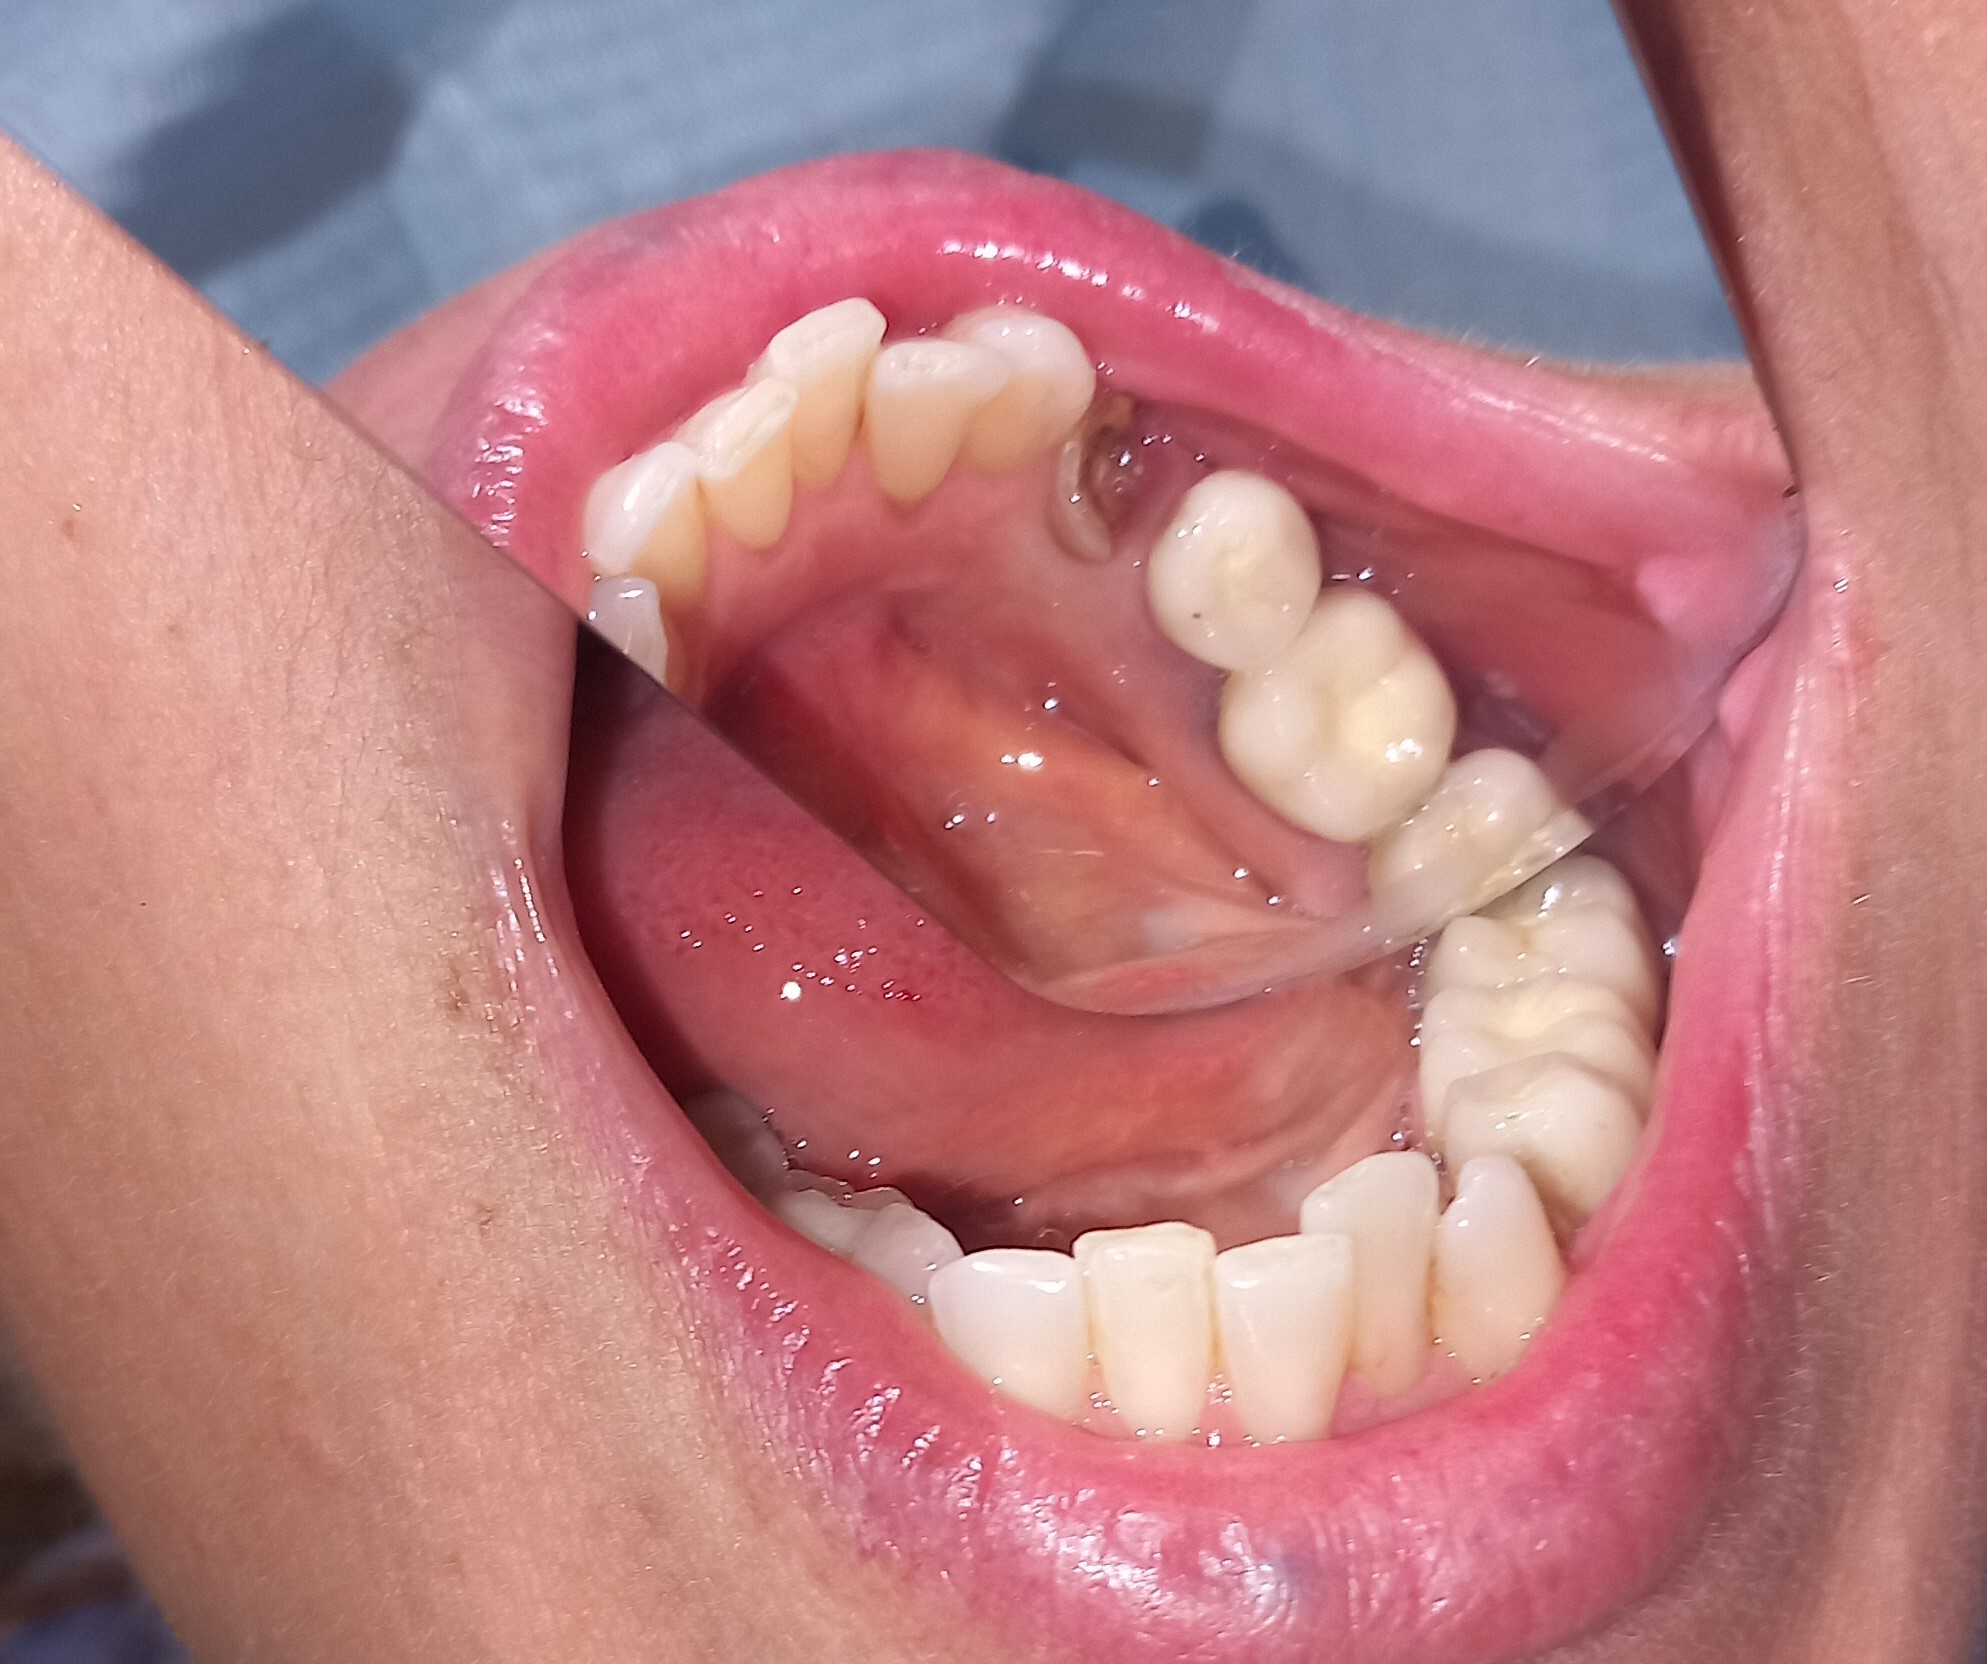

Ο ασθενής είχε πάρα πολλά χρόνια να επισκεφτεί τον οδοντίατρο. Πρόκειται για ένα απαιτητικό περιστατικό, κατά το οποίο ο ασθενής ήταν πολύ συνεργάσιμος καθώς ήθελε να αποκτήσει ένα όμορφο και λαμπερό χαμόγελο. Αρχικά εξάχθηκαν όσα δόντια δεν μπορούσαν να διατηρηθούν πλέον στο στόμα του ασθενή. Στη συνέχεια απονευρώθηκαν τα περισσότερα δόντια και ακολούθησαν ανασυστάσεις όλων των δοντιών. Εφόσον είχε αποκατασταθεί η φλεγμονή των ούλων λήφθηκαν αποτυπώματα και στάλθηκαν στον οδοντοτεχνίτη ο οποίος κατασκεύασε ολοκεραμικές θήκες, οι οποίες ήταν ενωμένες μεταξύ τους (ολοκεραμικό πέταλλο). Ο ασθενής φορούσε προσωρινή γέφυρα στο μεσοδιάστημα που χρειάστηκε ο οδοντοτεχνίτης να κατασκευάσει τη μόνιμη προσθετική εργασία.

Ο ασθενής είναι πολύ χαρούμενος με το λειτουργικό και αισθητικό του αποτέλεσμα. Πρέπει να αναφερθεί οτι όσο καιρό ο ασθενής δεν είχε δόντια δυσκολευόταν πολύ στην άρθρωση του λόγου.

ΠΡΙΝ

Ενδιάμεση κατάσταση αφού ολοκληρώθηκαν οι ανασυστάσεις δοντιών

Ολοκεραμικό πέταλο ζιρκονίου

ΜΕΤΑ